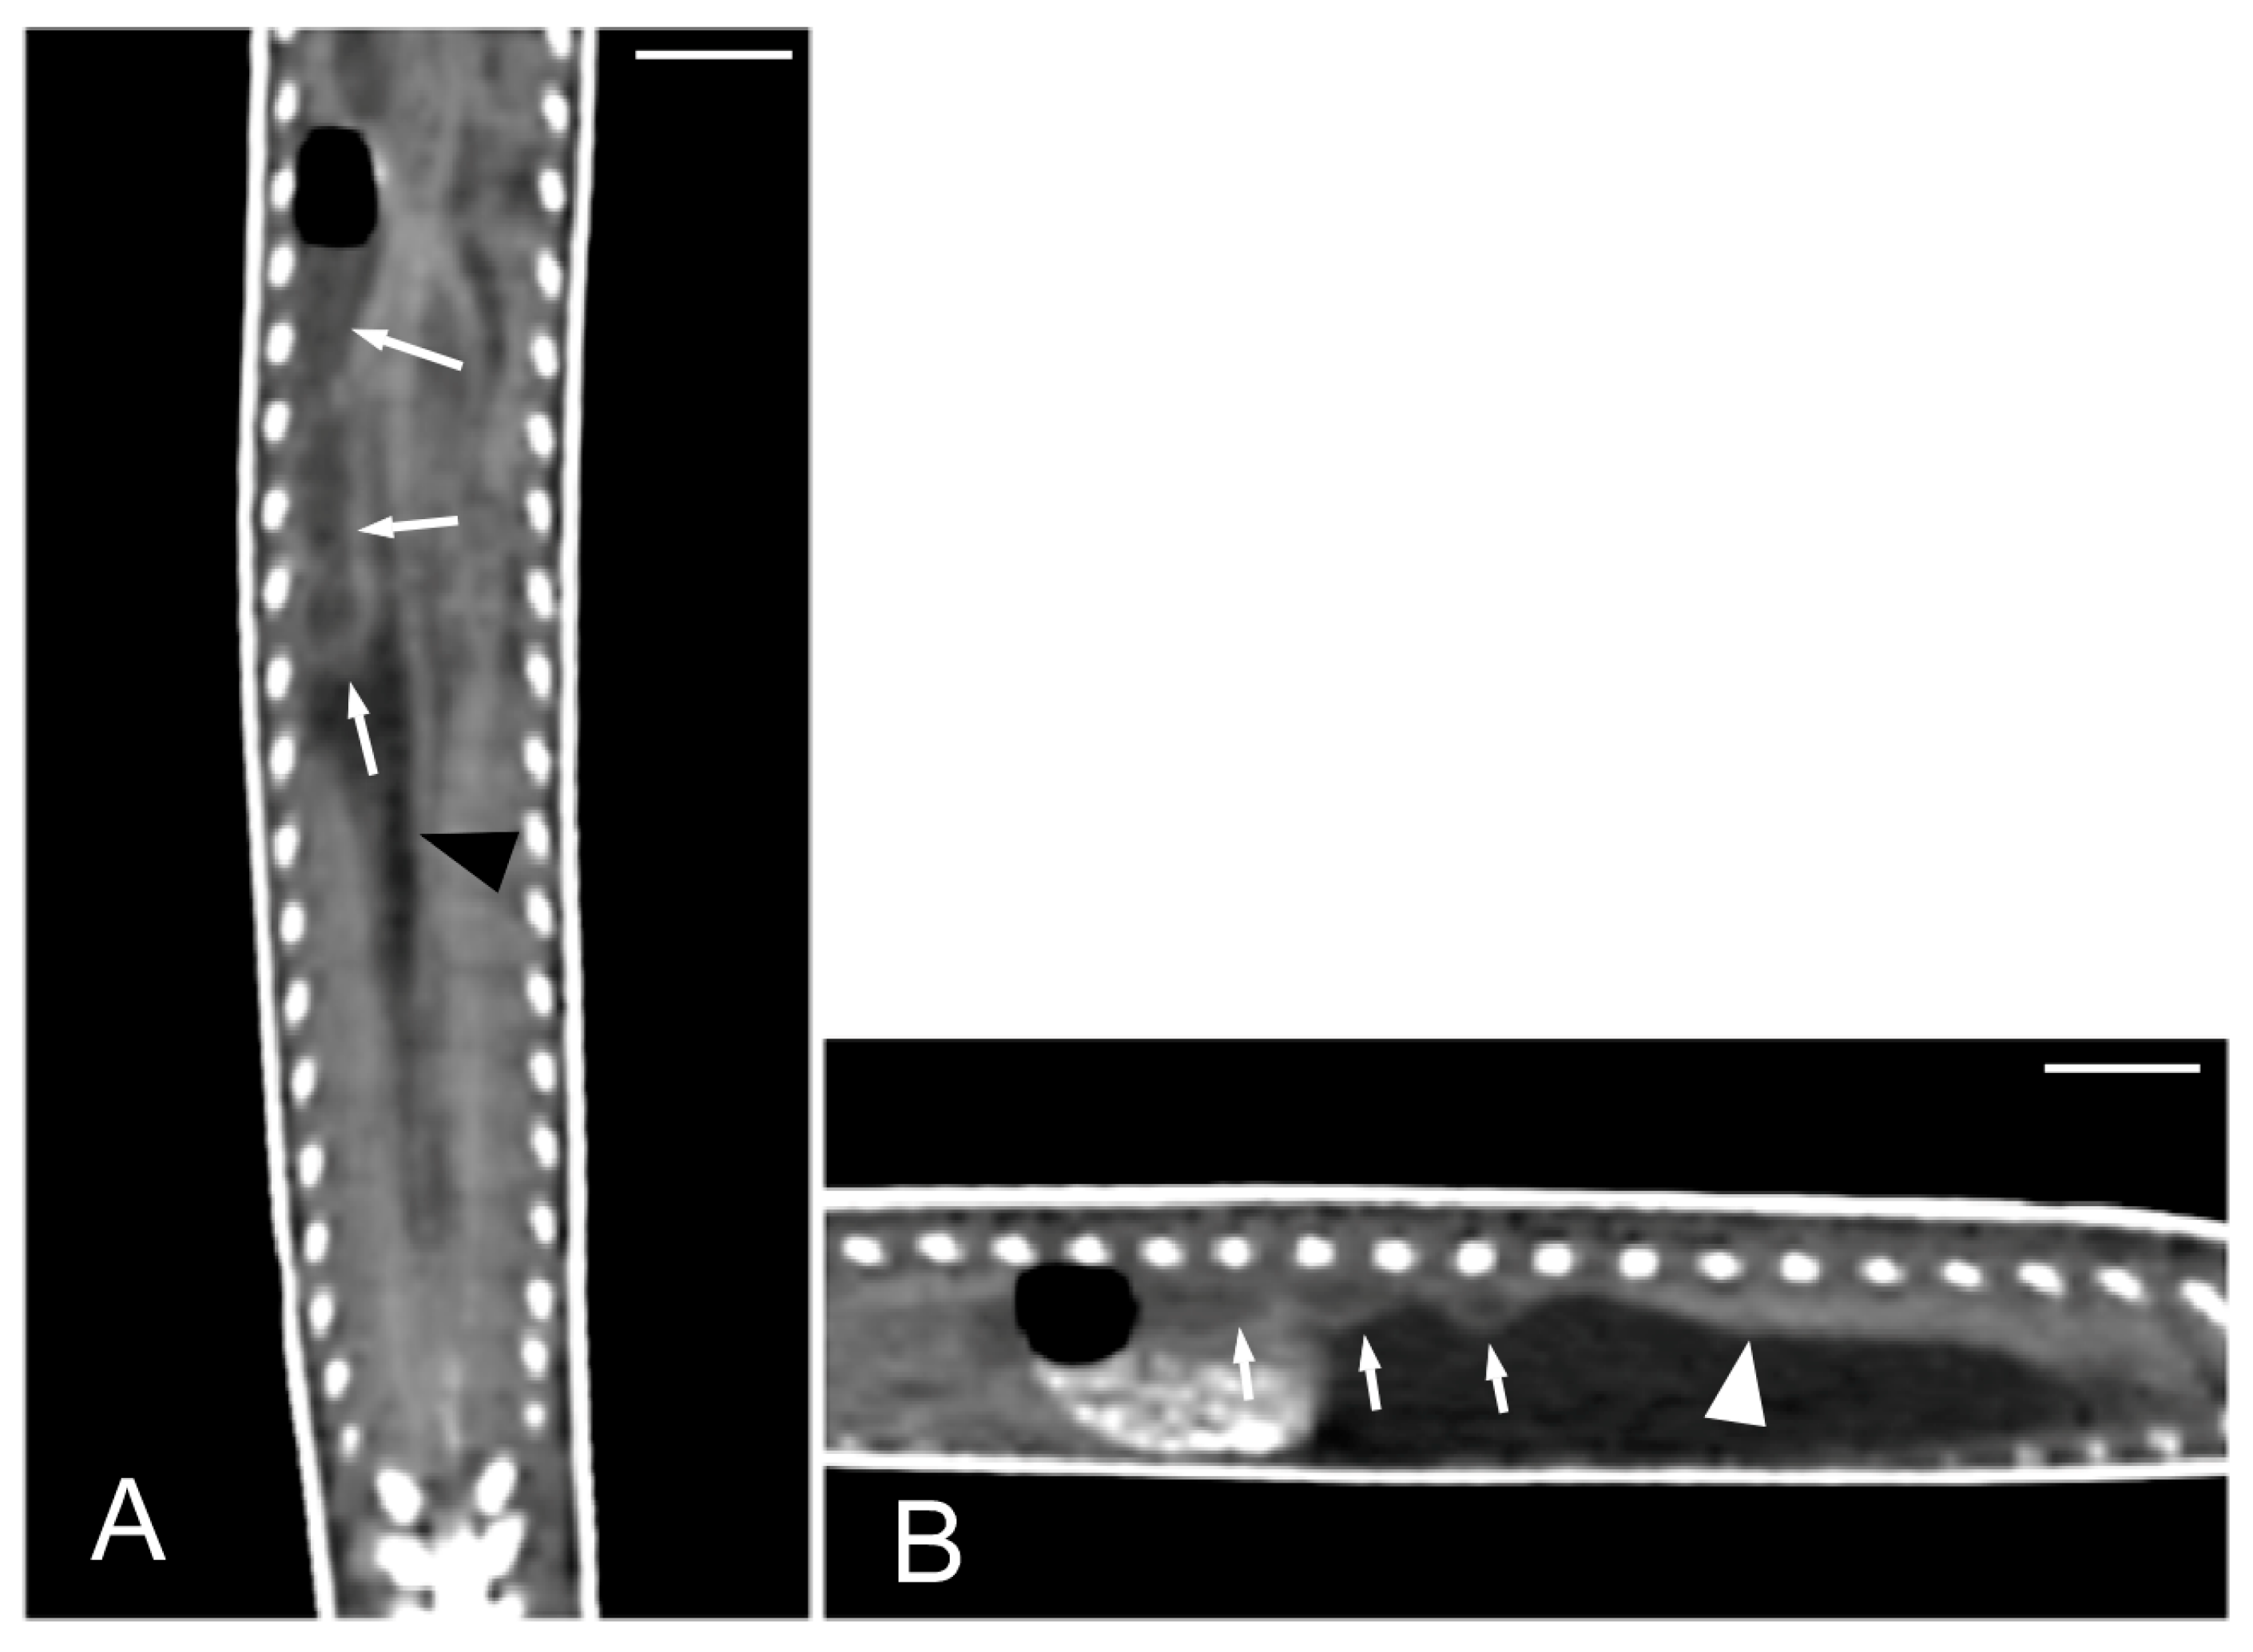

Concerning the CT images, the bifurcation of the trachea into the main bronchi was most clearly observed in the transverse plane (Figure 8A). The two lungs appeared as elongated structures with a reticular hypoattenuating area around an air-filled cavity. The distinction between the hypoattenuating area and just air was more distinctly identified in the transverse and dorsal planes using a postprocessing lung algorithm (Figure 8B,C). The 3D volume rendering using a postprocessing airways algorithm detailed the trachea and lungs (Figure 8D,E). Between the lungs, it was possible to identify those esophageal segments containing gas. On the contrary, those esophageal segments without intraluminal gas were indistinguishable from the surrounding soft tissues. The transverse and dorsal planes were the most useful for recognizing the esophagus (Figure 9). The liver appeared as an elongated organ with soft tissue attenuation located ventral to the caudal midsection of the lungs, on the right side of the stomach. Its margins were not well defined. The gall bladder was identified in the ventral part of the coelomic cavity as a hypoattenuating small oval structure surrounded by the hepatic parenchyma (Figure 10A). The differentiation between the gall bladder and the hepatic parenchyma was more evident in the postcontrast studies (Figure 10B–D). As in the case of the esophagus, the stomach and the small and large intestines were easily distinguished when containing intraluminal gas (Figure 11A) or hyperattenuating content (residual ingesta) (Figure 11B). The small and large intestines were located just caudal to the liver and the stomach, occupying approximately the caudal third of the coelomic cavity. The spleen and pancreas could not be identified when using CT.

Figure 8.

The CT images of Pseudopus apodus in the transverse (A,B) and dorsal (C) planes, and the 3D volume rendering showing the airways (D,E). Image (A) was obtained with a soft tissue algorithm and shows the main bronchi bifurcation (white arrow), while images (B,C) were postprocessed using a lung algorithm and show the peripheric hypoattenuating area (black arrowheads) around an air-filled cavity. The images (D,E) were postprocessed using the 3D volume rendering with airways algorithm and offer a detailed representation of the trachea (tr) and lungs (L). Bar = 10 mm.

Figure 9.

The CT images of Pseudopus apodus in the transverse (A) and dorsal (B) planes showing segments of the esophagus (arrowheads) with intraluminal gas. The esophagus is located between the lungs (L). Bar = 10 mm.